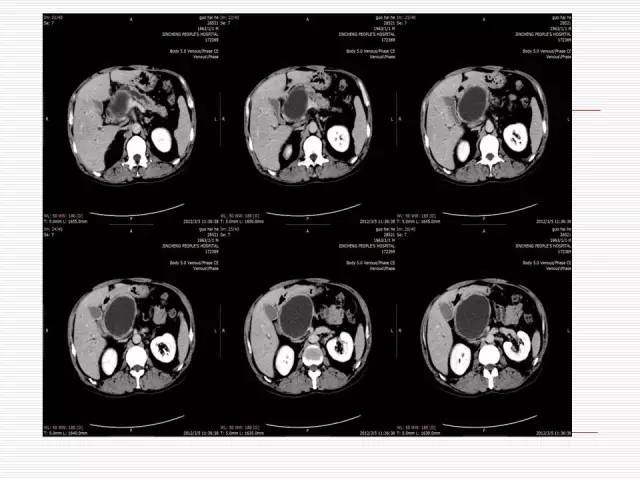

Case 1

Case 2

Case 3

Case1: 胰腺假性囊肿

Case2: 胰腺真性囊肿

Case3: 胰腺癌伴潴留囊肿

患者常有胰腺炎病史或胰腺外伤史,表现为单房囊性低密度区,少数可有分隔和钙化,囊壁一般较薄,无强化,也无壁结节,囊腔多与胰管相通,部分可伴有慢性胰腺炎的胰腺改变:胰腺萎缩、胰实质或胰管的钙化、胰管不规则扩张等。根据影像表现并结合临床病史及胰腺的继发改变,一般不难做出判断。

潴留囊肿:为胰腺导管近端梗阻,远端扩张形成,因此囊肿与胰导管相通,多由近端肿瘤或结石引起。

真性囊肿:少见,为胰腺导管发育异常所致,内衬完整的内皮,为扁平或低柱状上皮。

单发或多发,囊腔不与胰管相通,囊内无间隔及软组织结节,可以单纯发生在胰腺,也可同时伴有肝肾的多囊病或VHL病(Von Hippel-Linda Disease),最终确诊要依靠病理。

胰腺癌囊性变:多由肿瘤组织阻塞导管引起潴留性囊肿或由肿瘤发生坏死液化而形成囊腔。

潴留性囊肿的近端常有实性肿块,肿瘤坏死囊变,肿瘤实性组织构成囊壁,故囊壁不完整,厚而不规则,或无明确囊壁显示。